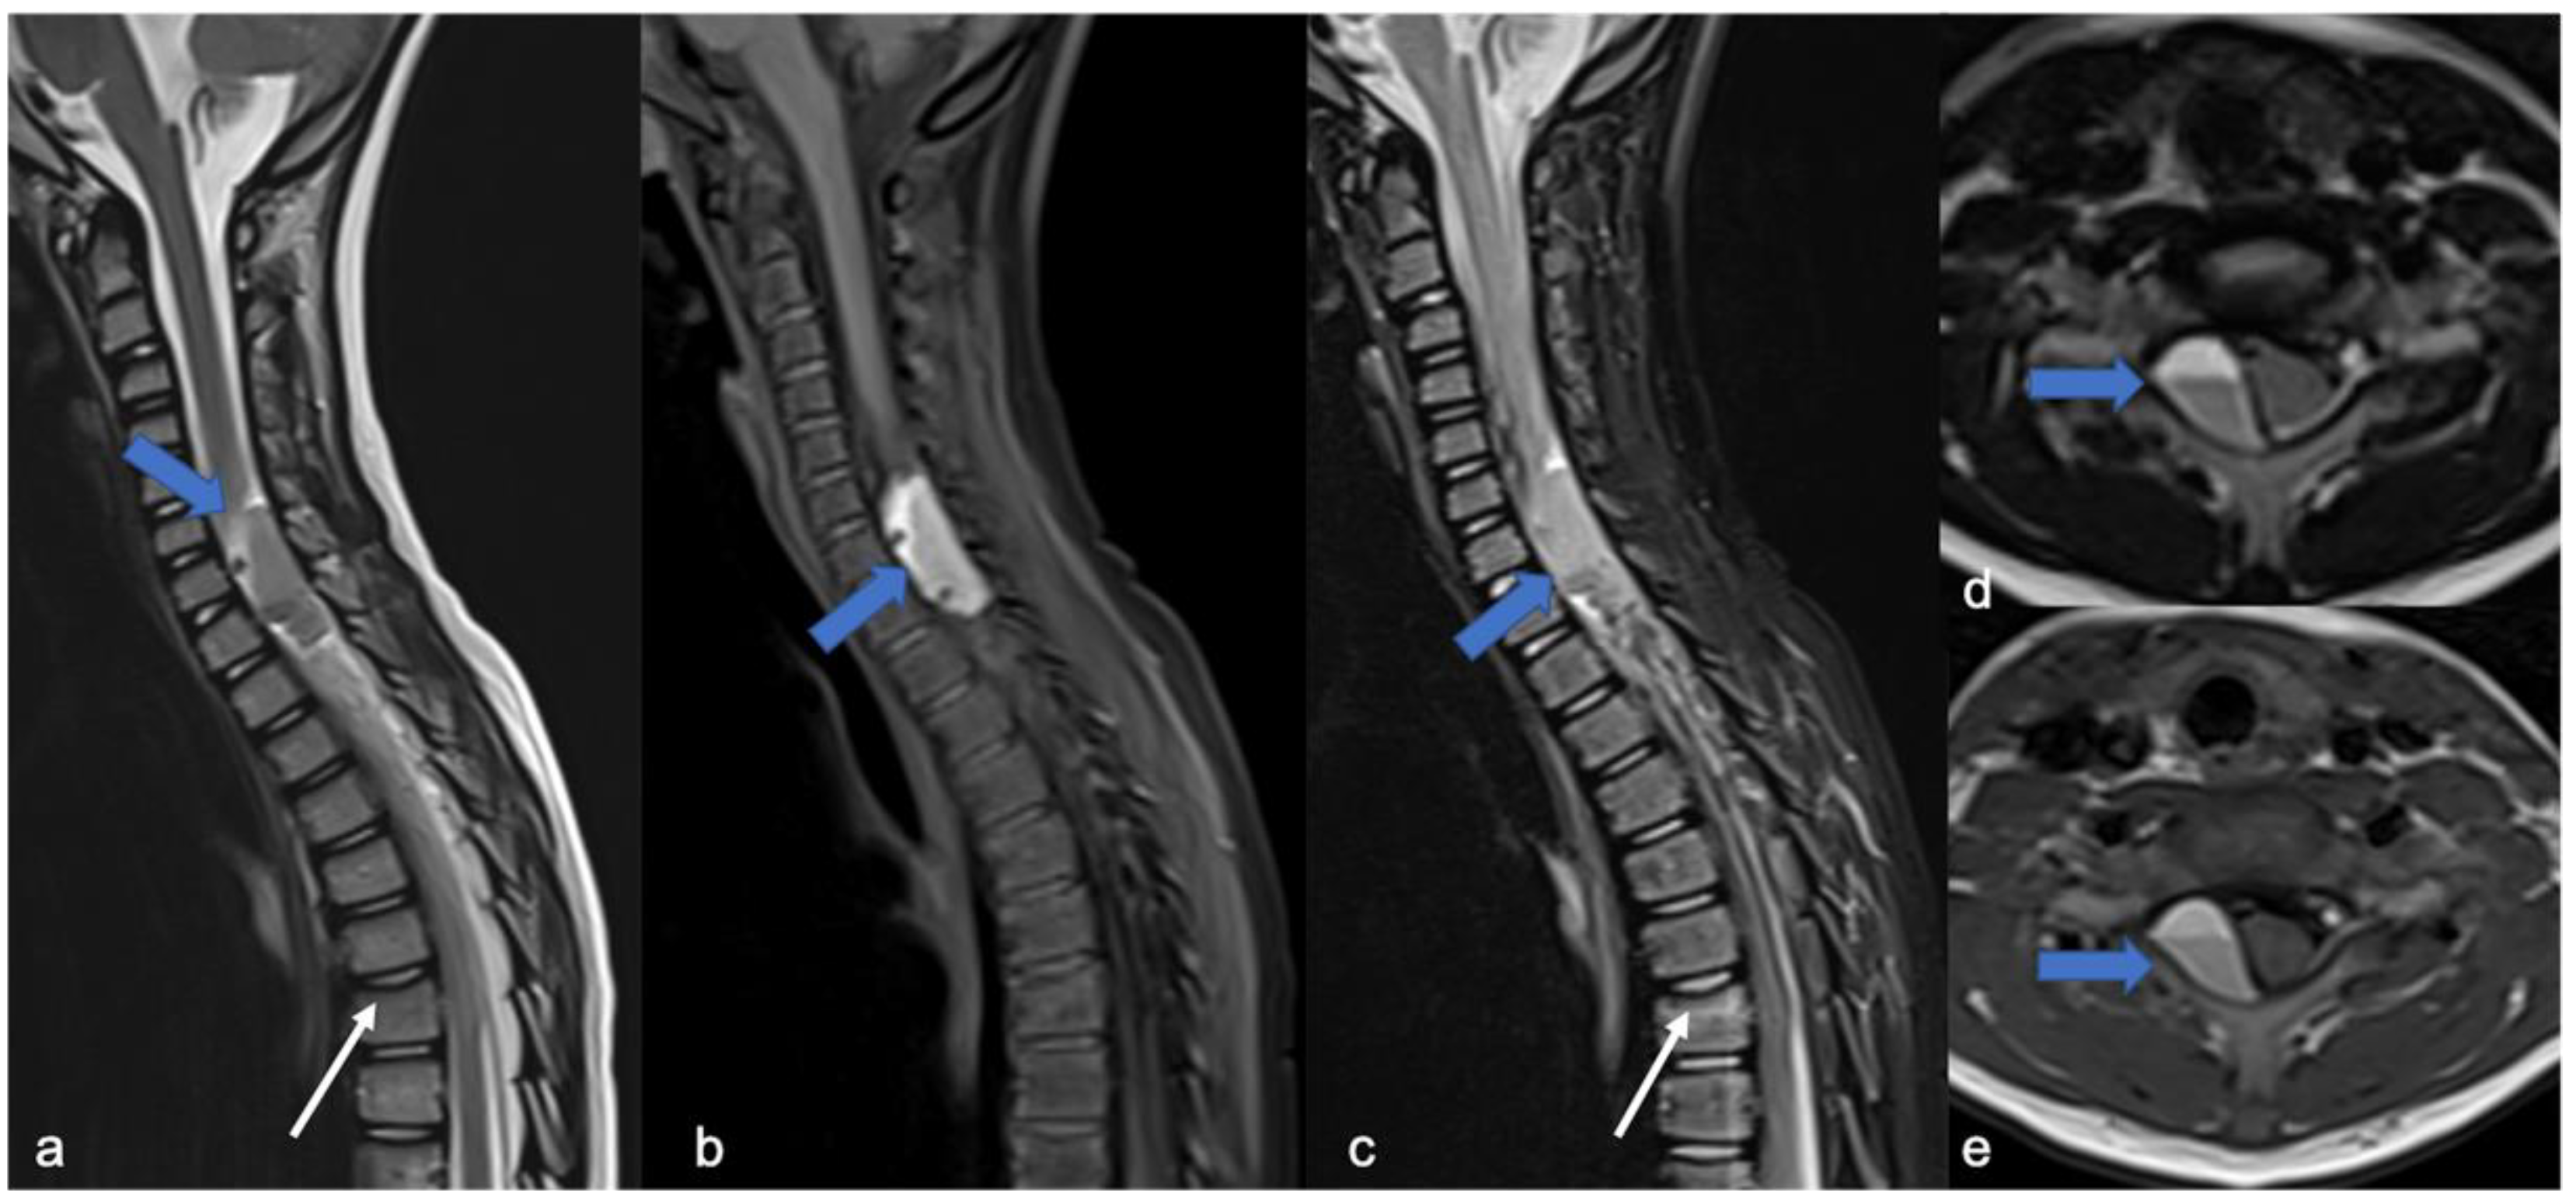

As low-grade tumors with variable epicenters, hemangioblastomas are uncommon in children. Neoplastic growth is slow and can be intramedullary (75% of cases), but also intradural when tumors arise from nerve roots or extradural [1]. MRI usually shows a tumor with (i) predominantly solid component and clear margins, (ii) rich vascular support, and (iii) avid enhancement and sometimes cysts (Figure 9) and bleeding [7]. Before surgical excision, it is useful to perform a medullary angiography to identify arterial feeders that can be embolized. Hemangioblastomas are commonly found in patients with von Hippel-Lindau (VHL) syndrome and findings of hemangioblastoma should prompt investigation for VHL. Hemangioblastomas are formed by “stromal” cells (with VHL mutation) and rich blood vessels (without VHL mutation). This evident angiogenesis is related to the activation of angiogenetic factors (VEGF, HIF) in the stromal cells [36]. Surgical excision is the treatment of choice and can be associated with a preventive embolization [7].

Figure 9.

Hemangioblastomas in a fifteen-year-old child with cystic solid components located in the cervical–dorsal junction. Sagittal T2-weighted (a) and post-contrast T1-weighted (b) images demonstrate the enhancing solid nodular components (arrows) and the cystic component (arrowhead). After two years (c,d), the cystic component increased while the solid component remained stable.

Meningiomas, rare in children, make up only 3% of pediatric SNC tumors [45] and are closely related to the diagnosis of NF2; it is estimated that 20% of NF2 patients harbor spinal meningiomas. Meningiomas in NF2 are typically WHO grade 1, slow-growing, benign tumors. When present, meningiomas in NF2 patients are often multiple, which contributes significantly to morbidity and mortality. The “clear cell meningioma (CCM)” (WHO grade II) is a typical pediatric/juvenile spinal meningioma and represents the most common histological subtype of sporadic pediatric spinal meningioma [3]. They are characterized by early local recurrence and cerebrospinal fluid metastasis. The World Health Organization defines CCM as a grade II cancer. Its incidence rate in children is higher than that in adults, who may manifest aggressive features such as recurrence and CSF dissemination [46,47,48,49]. The MRI features include dural tail, isointensity in T1 and T2 compared to the spinal cord, clear margins, and homogeneous enhancement (Figure 10) [3]. Outcome is closely related to surgery: gross total resection is associated with a good clinical outcome, while subtotal resection or partial resection could be associated with recurrence or growth of the residual lesion with clinical progression even 60 months after the first surgery (long-term recurrence) [50].

Figure 10.

Gadolinium-enhanced T1-weighted image. Craniocervical junction meningioma (arrow) characterized by dural base, well-defined margins, and intense and homogeneous enhancement. Compression and anterior dislocation of the bulb and cervical cord are evident (arrowhead).